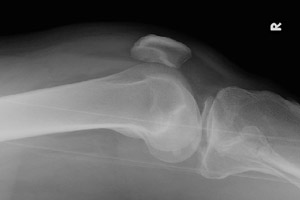

- Click on the image for a larger versionBOblique radiograph of the knee. The fracture of the tibia is visualized.